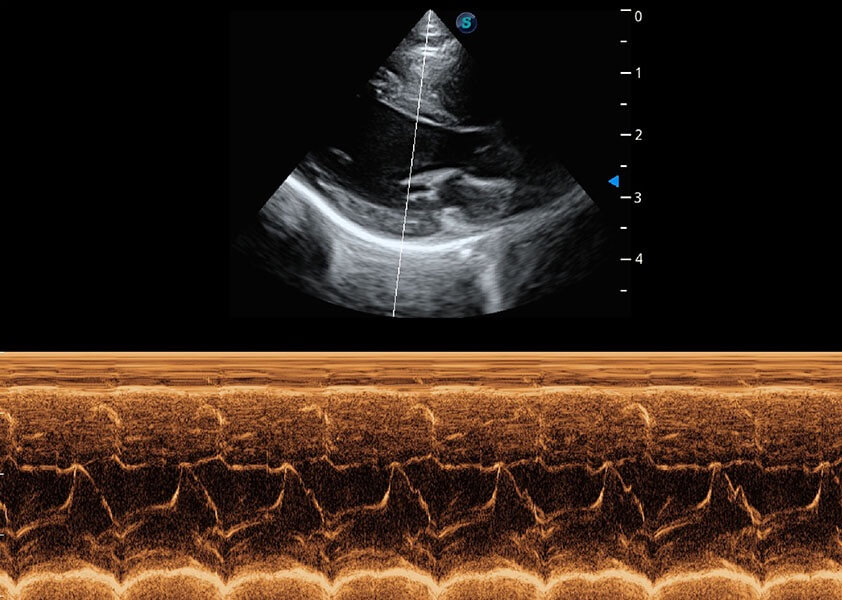

ProPet 60 作为一款高端台式动物超声设备,为动物医生的日常诊断提供了一系列贴合动物临床需求、解决临床实际问题的高级成像功能。凭借全系列高清探头,满足医生对腹部、心脏、生殖、浅表、肌骨等成像的所有需求,切实帮助您提升检查效率,提高诊断信心。

兽用彩色多普勒超声诊断系统